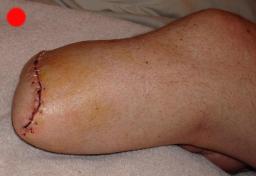

Postoperative (15th) images of left ankle

On May 30th 2007 exactly 2 years and 2 days from the day that Liam had his skydiving accident, doctor Ott removed the lower part of Liam’s left

leg using what is described as an Ertl procedure. The Ertl procedure results in a residual limb that is stronger and has a greater ability to load bear.

It is expected that Liam’s fatigue will be greatly reduced as a result of the Ertl procedure. The X-Rays show the best details associated with the Ertl

procedure. It can clearly be seen that a piece of bone (from the fibula) has been used to bridge the gap between tibia and fibula. What can not be seen

is the amount of tissue and muscle that was used (found normally in the lower part of the limb) to form a sort of pocket surrounding the remaining bone.